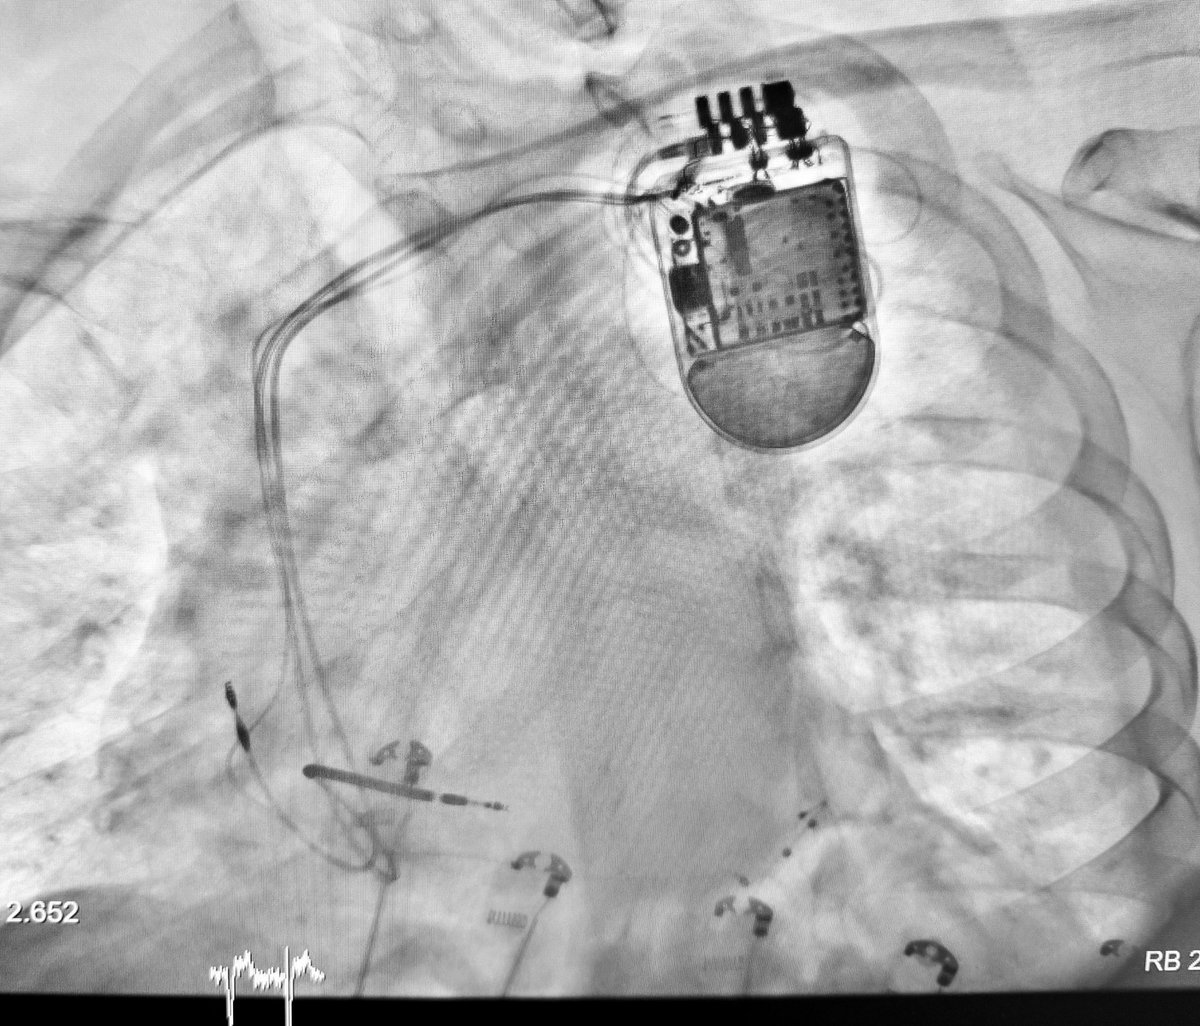

Upgrade from an DDD ICD to CRT-D #Abbott in a patient with ischemic cardiomyopathy and 100% RV stimulation. Initial QRS 200ms, final 104 ms. Hospital Dr. Jose Molina Orosa Lanzarote @ArritmiasJMO #Cardiology